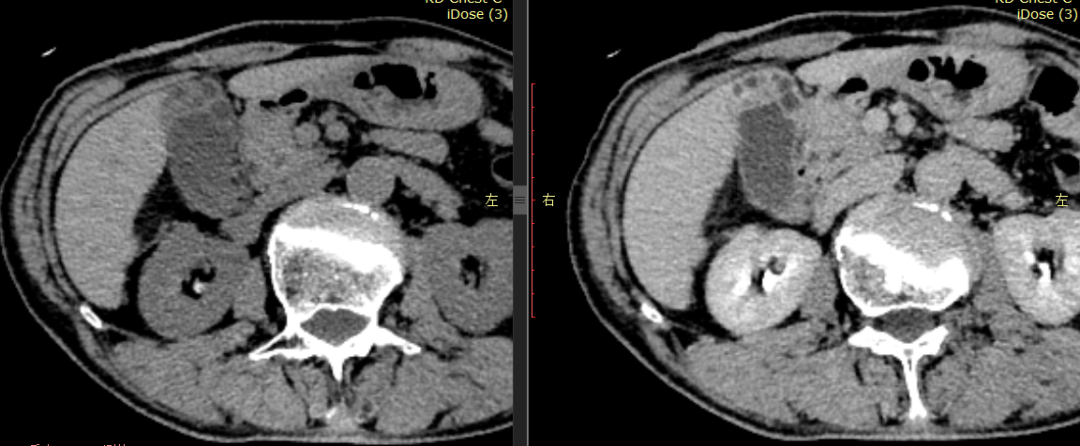

CASE 1